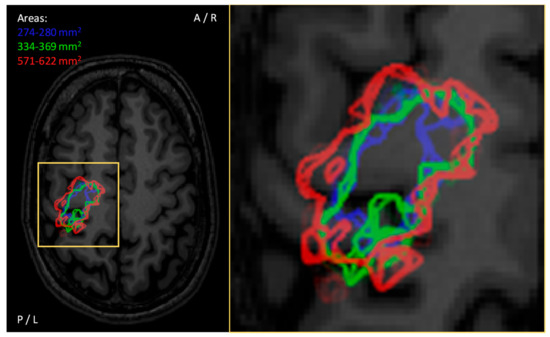

- Julkunen, P. Methods for estimating cortical motor representation size and location in navigated transcranial magnetic stimulation. J. Neurosci. Methods 2014, 232, 125–133. [Google Scholar] [CrossRef]

- Chernyavskiy, A.Y.; Sinitsyn, D.O.; Poydasheva, A.G.; Bakulin, I.S.; Suponeva, N.A.; Piradov, M.A. Accuracy of Estimating the Area of Cortical Muscle Representations from TMS Mapping Data Using Voronoi Diagrams. Brain Topogr. 2019, 32, 859–872. [Google Scholar] [CrossRef]